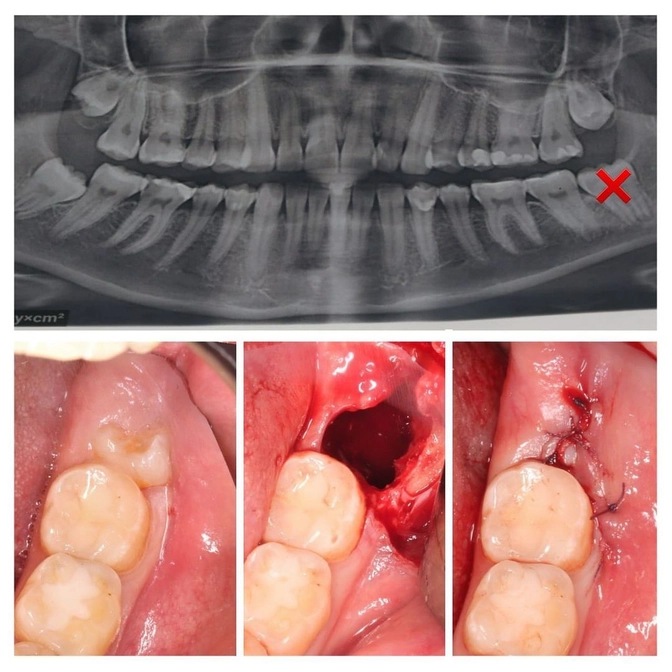

Работа в копилке нашего стоматолога-хирурга Алины Ситдиковой.

Пациентка взрослая.

"Восьмерка" при прорезывании наполовину оказалась закрыта мягкими тканями и доставляла боль и дискомфорт при приеме пищи.

Выход — удаление.

✔️Сначала делаем снимок, на котором видно, какие корни у зуба, насколько глубоко он сидит в челюсти, ретенирован и/или дистопирован.

✔️В нашем случае "восьмерка" была закрыта десной и костной тканью, требовалось рассечение.

✔️Зуб удалили.

✔️Образовалась большая раневая поверхность — необходимо наложить швы.

Их удаляют через 5–7, иногда 10, дней после операции, т.к. в них легко может застрять пища и присоединится инфекция.